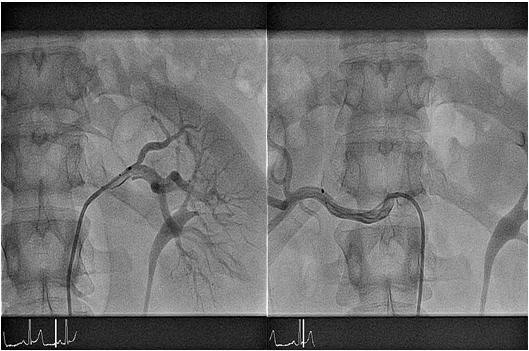

Εικ 1. Νεφρική αγγειογραφία που αναδεικνύει  τον καθετήρα ablation Semlicity  στη αριστερή ( αρ. τμήμα)  και στη δεξιά (δε. τμήμα) νεφρική αρτηρία.

Η εισαγωγή του ασθενούς περιλαμβάνει νοσηλεία μίας ημέρας. Μετά τον κλινικό έλεγχο ο ασθενής υποβάλλεται σε υπερηχογράφημα νεφρών και triplex νεφρικών αρτηριών προς αποκλεισμό στενώσεως νεφρικής αρτηρίας. Η επέμβαση διενεργείται στο Αιμοδυναμικό Εργαστήριο.  Yπό τοπική αναισθησία παρακεντείται η μηριαία αρτηρία και απεικονίζονται οι νεφρικές αρτηρίες. Ακολουθεί εισαγωγή στη νεφρική αρτηρία καθετήρα απονεύρωσης (Simplicity, Medronic) ο οποίος είναι συνδεδεμένος εξωτερικά με τη γεννήτρια της κατάλυσης.  Χορηγούνται σε έξι θέσεις στο αγγείο, στα σημεία που μετρηθούν αντιστάσεις μεγαλύτερες από 250 Ohm, συνεδρίες υψίσυχνου εναλλασόμενου ρεύματος έως 8 Watts διάρκειας  120 δευτερολέπτων η καθεμία. Η πρώτη θέση χορηγήσεως είναι στο άπω τμήμα της νεφρικής αρτηρίας και διαδοχικά ο καθετήρας αποσύρεται κατά 5 mm και στρέφεται κατά 90 μοίρες προς την επόμενη θέση.  Η ίδια διαδικασία επαναλαμβάνεται και στην άλλη νεφρική αρτηρία. Μετά την ολοκλήρωση της πράξεως αφαιρείται ο καθετήρας  από τη μηριαία αρτηρία και ο ασθενής μεταφέρεται στο δωμάτιο του κινητοποιούμενος μετά από λίγες ώρες.  Εξέρχεται της κλινικής την επομένη.